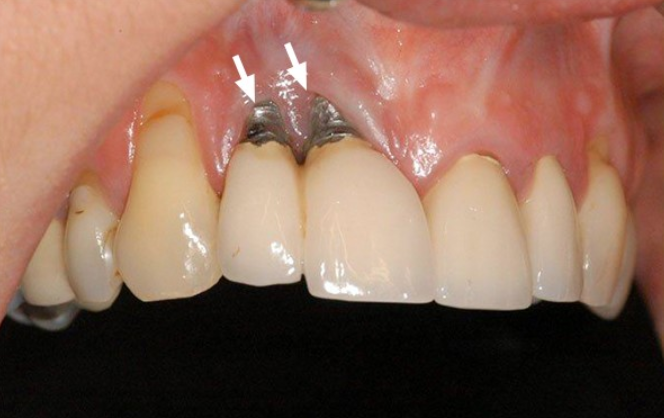

Trong implant Phuong phap phuc hinh rang mat hien dai va an toan Mat rang khong chi anh huong toi tham my ma con lien quan truc tiep về sức khỏe răng miệng như tiêu xương hàm, sai khớp cắn, giảm khả năng ăn nhai. Giữa nhiều phương pháp phục hình hiện nay, trồng implant được đánh giá là giải pháp tối ưu bởi khả năng khôi phục răng mất gần như răng thật cả về hình dáng lẫn chức năng. Đây là công nghệ hiện đại, mang lại sự bền vững lâu dài, giúp bệnh nhân lấy lại nụ cười tự tin và nâng cao chất lượng cuộc sống. Trồng implant là gì và cơ chế hoạt động Trồng răng cấy ghép implant là kỹ thuật đặt trụ titanium vào xương hàm, thay thế cho chân răng thật đã mất. Sau một thời gian tích hợp xương, trụ sẽ gắn chặt với mô xương, tạo nền tảng để bác sĩ phục hình mão sứ bên trên.

Theo “Fundamentals of Fixed Prosthodontics”, Implant không chỉ phục hình răng mất mà còn có tác dụng duy trì cấu trúc xương, ngăn ngừa tiêu xương và biến dạng khuôn mặt. Đây là điểm vượt trội so với cầu răng hoặc hàm giả tháo lắp. Vì sao trồng implant được nhiều người lựa chọn Phục hồi chức năng ăn nhai tối ưu Trụ Implant tích hợp với xương hàm tạo nên độ vững chắc, cho phép bệnh nhân ăn nhai thoải mái mà không lo lung lay hay rơi rớt. Đảm bảo thẩm mỹ tự nhiên Mão sứ gắn trên Implant được thiết kế có màu sắc và hình dáng tương tự răng thật, khó nhận biết sự khác biệt. Ngăn chặn tiêu xương hàm Mất răng lâu ngày khiến xương hàm tiêu dần. Trồng răng implant kích thích xương phát triển, giữ vững hình dáng gương mặt.